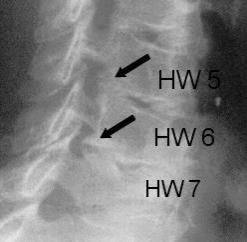

Durch die Untersuchung und Anamneseerhebung ergeben sich wichtige Hinweise auf die Ursachen der Beschwerden. Hieran orientiert sich auch maßgeblich die Empfehlung für oder gegen eine Operation. Ergänzend sind häufig konventionelle Röntgenaufnahmen sowie eine Kernspintomographie sinnvoll. Knochenveränderungen werden besser mit der Computertomographie erfasst. Besteht der Verdacht auf eine Rückenmarkserkrankung oder eine Störung der Nervenfunktion wird eine elektrophysiologische Untersuchung (evozierte Potentiale) organisiert. Hierbei wird, ähnlich wie bei einem Stromkabel, die Durchgängigkeit der Nervenbahnen gemessen.

Der Eingriff wird in Vollnarkose und Bauchlagerung mit Überstreckung von Kopf- und Halswirbelsäule durchgeführt. Nach sorgfältigem Ablösen der sehr kräftigen Nackenmuskulatur von den hinteren Anteilen der Halswirbelsäule wird unter Röntgenkontrolle die richtige Etage verifiziert. Anschließend werden von hinten mit Mikrofräsen und Stanzen die aneinander grenzenden seitlichen Anteile der Wirbelhalbbögen entfernt. Der geschaffene, knöcherne Defekt ist in aller Regel kleiner als ein Fingernagel und verhilft dem Patienten zur Beschwerdefreiheit.